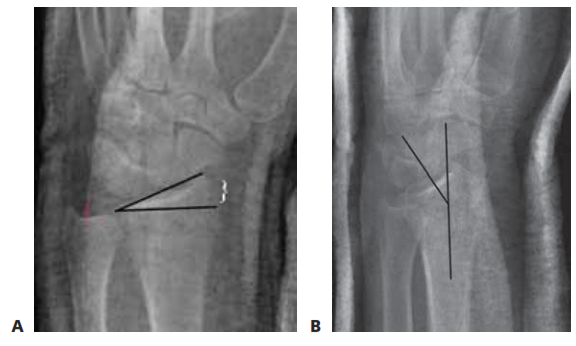

Page 6 of 13Traumatic Carpometacarpal (CMC) Joint Injuries: Anatomy, Biomechanics & Clinical Management